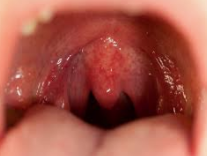

목젖 늘어짐

간혹 목젖이 평소보다 늘어져있는것처럼 보일때가 있습니다. 이럴때 대수롭지 않게 넘기는 경우가 많은데 건강에 이상이 있다는 신호이기 때문에 치료가 필요한 증상입니다. 오늘은 목젖 늘어짐 증상의 원인 및 치료방법에 대해서 알려드리겠습니다.

| 목젖 늘어짐 원인

목젖이 늘어나는 원인에는 목에 염증이 생겼을때 입니다. 평소 편도가 좋지 않은 경우에도 해당이 됩니다. 목이 붓는 원인 중에는 피로가 많이 쌓였거나 면역력이 많이 떨어졌을때 가장 많이 나타나는 증상입니다.

그리고 입안에 청결상태가 좋지 않을때 세균에 의한 염증이 발생될 수 있습니다.